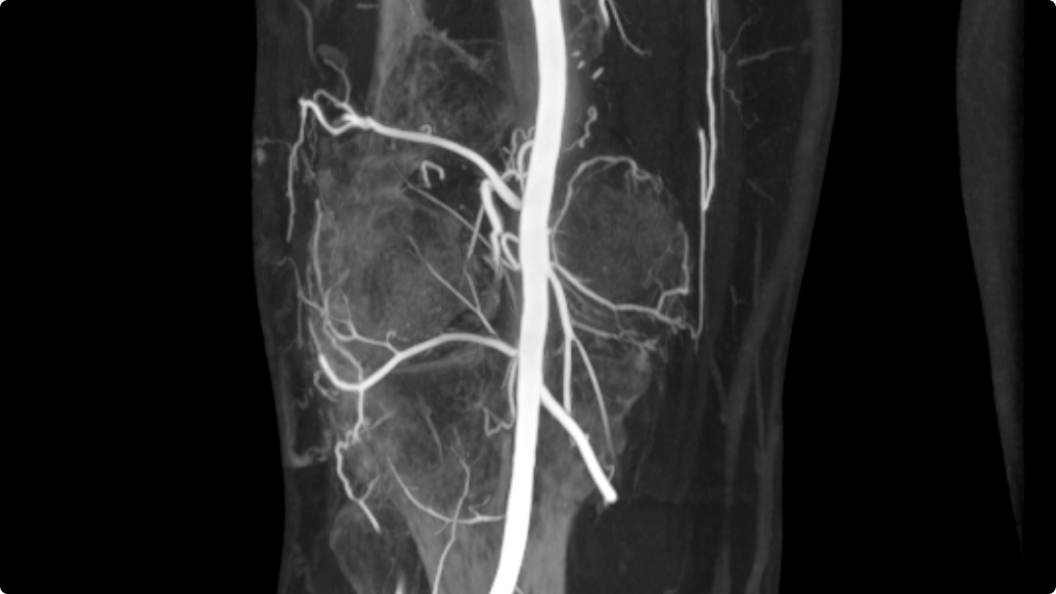

MAR11

Reduzierung von Metallartefakten, Optimierung der Bildqualität

MAR11 (Metallic Artifact Reduction, Metallartefaktreduktion) ist eine fortschrittliche Technologie zur Reduzierung von Artefakten, die durch Metallgegenstände im Körper, zum Beispiel Implantate, verursacht werden. Diese Artefakte können wichtige anatomische Details verdecken. Dies erschwert es dem Klinikteam, Diagnosen zu stellen und Behandlungen genau zu planen.

MAR11 gewährleistet eine verbesserte Bildqualität und ist demnach ein wertvolles Instrument zur Verbesserung der Genauigkeit und Sicherheit minimalinvasiver Verfahren.